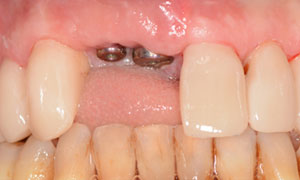

L’incisive centrale droite est mobile et disgracieuse. Les dents voisines du patient sont colorées et porteuses d’anciennes résines.

L’incisive latérale droite est porteuse d’un kyste important. Une maladie parodontale chronique généralisée génère des mobilités dentaires et des saignements gingivaux.

Le traitement parodontal non chirurgical a stabilisé la maladie parodontale et a permis la pose de deux implants en sites de deux incisives et de facettes sur les dents voisines.

Le patient a retrouvé l’esthétique de son sourire et le confort.